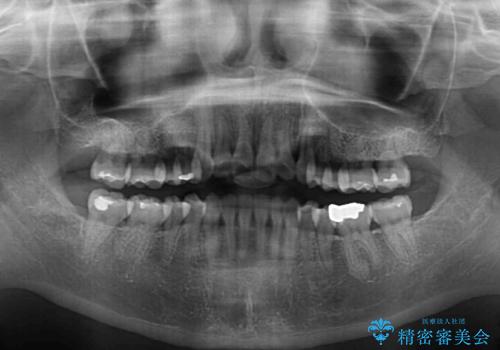

インビザラインでの歯列全体の後方移動は時間がかかりますが、しっかりと装着時間を守っていただいたので、スッキリとした口元に仕上げることができました。